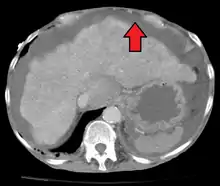

Ultrasound investigation is often done before attempts to remove fluid from the abdomen. This may reveal the size and shape of the abdominal organs, and Doppler studies may show the direction of flow in the portal vein, as well as detecting Budd-Chiari syndrome (thrombosis of the hepatic vein) and portal vein thrombosis. The sonographer also can estimate the amount of ascitic fluid, and difficult-to-drain ascites may be drained under ultrasound guidance. An abdominal CT scan is more accurate than a sonogram to reveal abdominal organ structure and morphology.[11]

- Grade 1: mild, only visible on ultrasound and CT